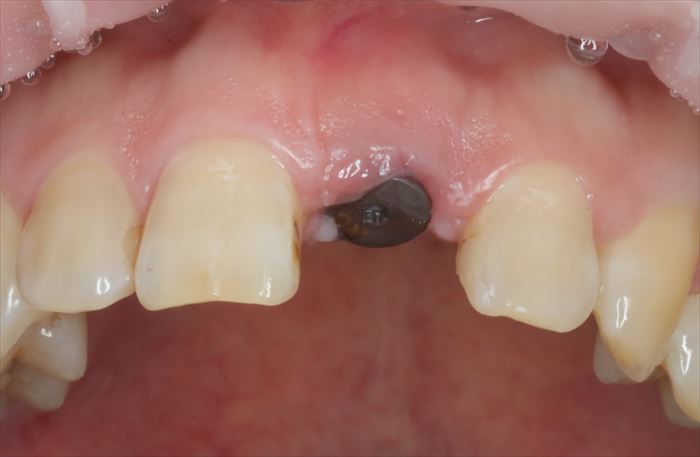

ヒーリングキャップを外しました。

歯肉はヒーリングキャップに沿って治癒しています。